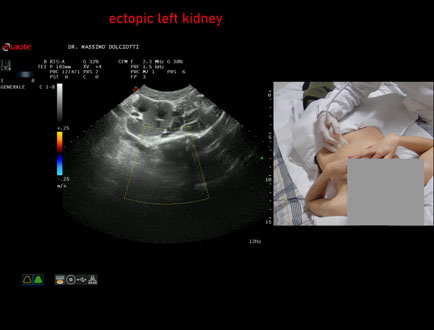

Data inserimento: 31/03/2026

Ecografia del: 16/03/2026

Strumento: Esaote MyLab Eight

Sonda: Convex Multifrequenza 1-8 MHz

Età Paziente: M 12 anni

Motivazione dell'esame: riscontro occasionale di ectopia renale sinistra

Commento all'esame: le immagini ed il video documentano il rene sinistro ectopico in sede pelvica, di ecostruttura regolare e morfovolumetria normale, con diametro bipolare di 99 mm (v.n. 90-120 mm) x 37 mm, non dilatazione della via escretrice sinistra.

Conclusioni: rene sinistro ectopico (ectopic left kidney).